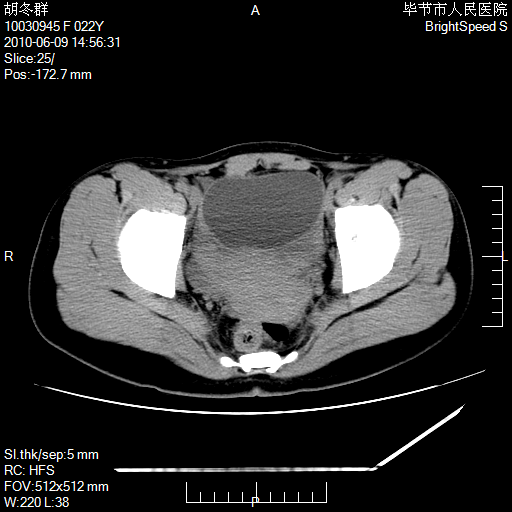

患者23岁,发现腹部包块3月。

左侧卵巢囊腺瘤或囊腺癌

盆腔内囊性占位性病变;考虑左侧卵巢囊腺瘤。

有分隔、壁薄,支持考虑左侧卵巢囊腺瘤。

左侧卵巢浆液性囊腺瘤。

支持考虑左侧卵巢囊腺瘤;宫腔积液。

有分隔、壁薄,支持考虑左侧卵巢囊腺瘤。排尿后,膀胱缩小,由于重力作用,肿块下移就到了膀胱位置,很好理解。